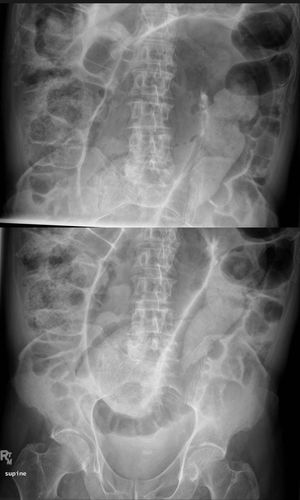

85 yr old male presents to the emergency room abdominal distention and obstipation. He has had severe bowel obstructions in the past. Physical examination reveals peritonitis. Abdominal radiographs are ordered as part of the patient's work up.* *What is the Diagnosis?*